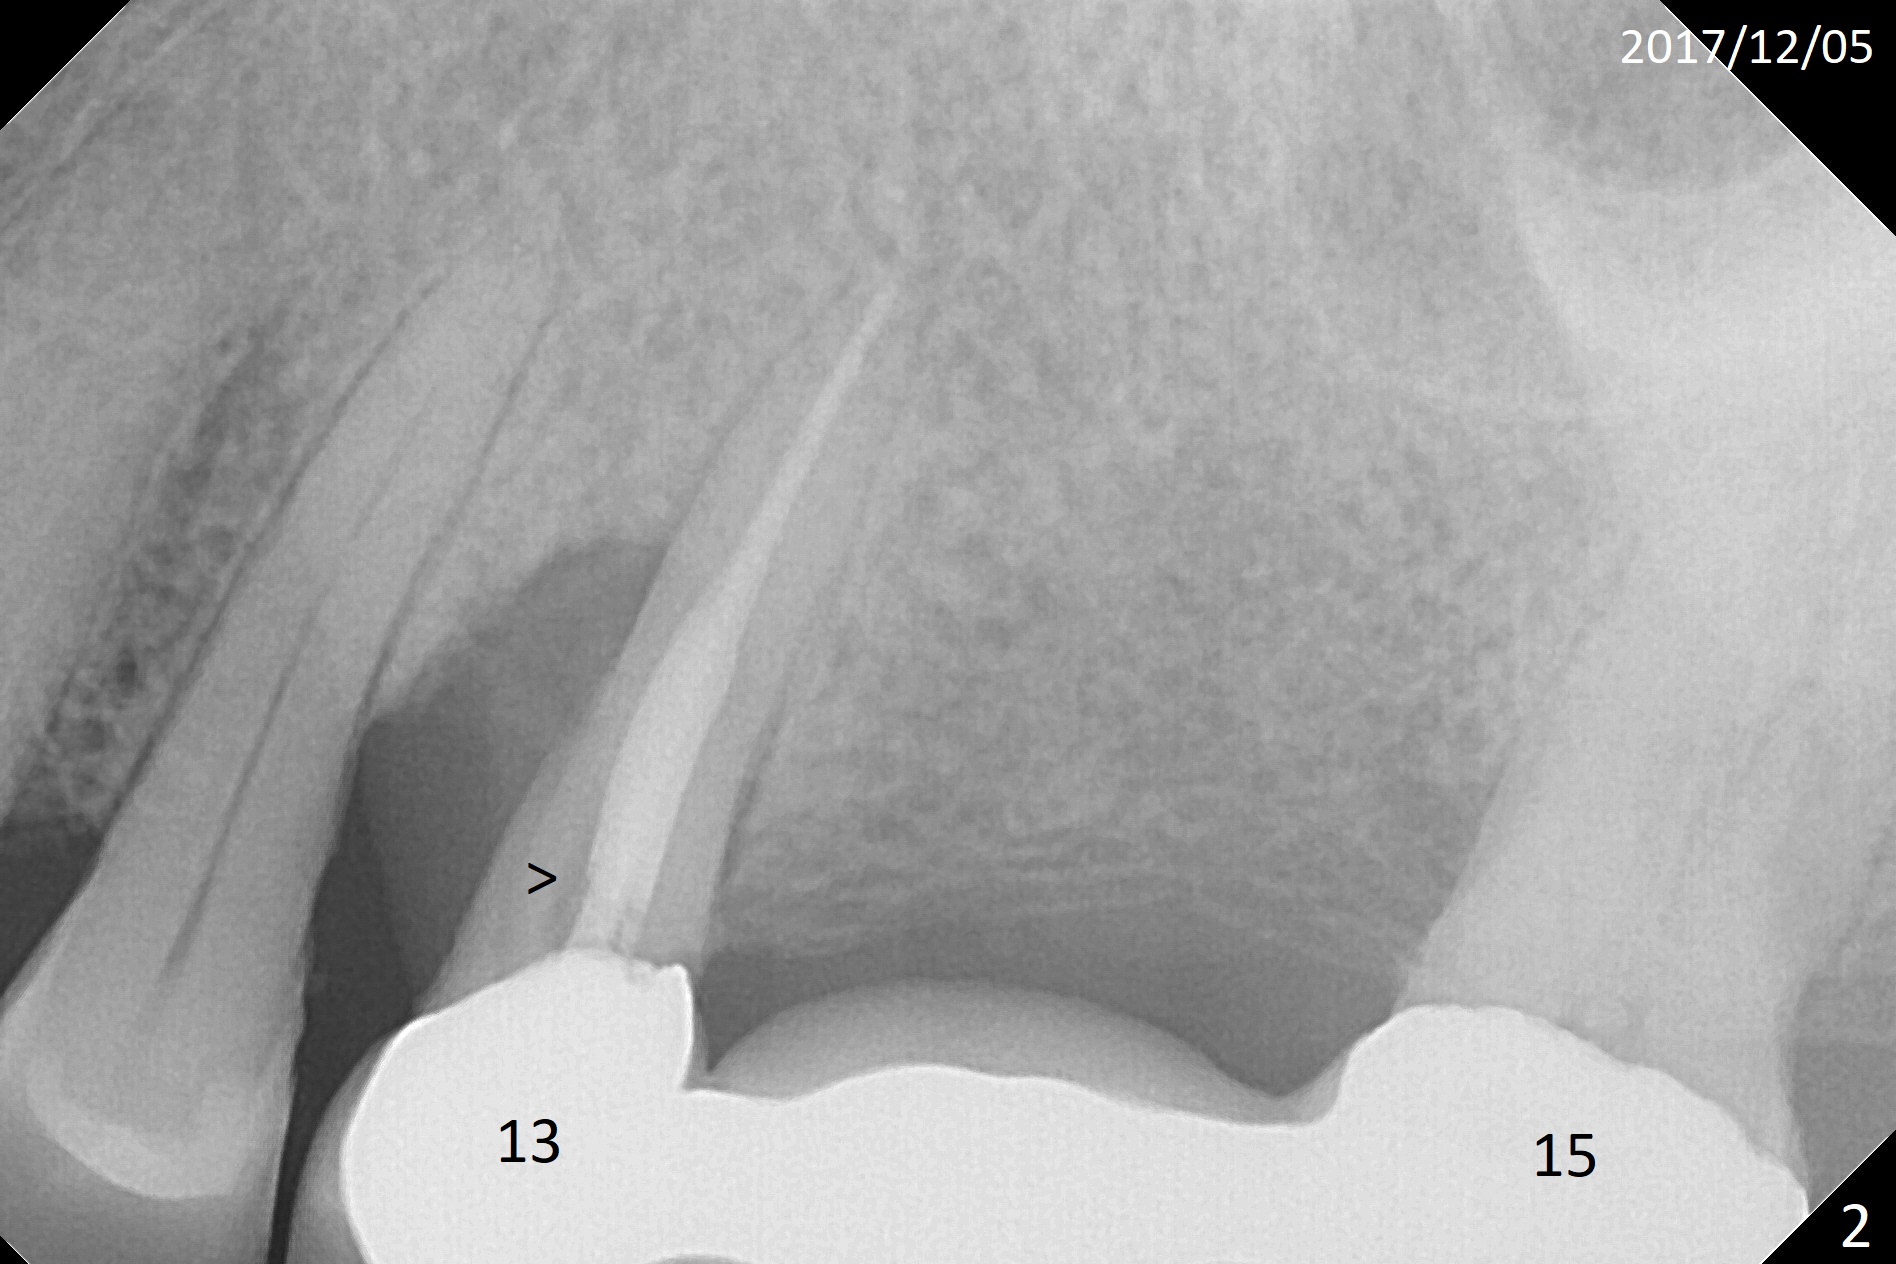

A 66-year-old woman is a bruxer/grinder. She loves chewing bone and eating nuts. The tooth #2 has exfoliated on its own, while the tooth #3 had periradicular bone loss (Fig.1). The upper left FPD is loose because of root fracture at #13 (Fig.2 >). Note the long alveolus. The mesial root of the tooth #30 has been fractured with severe bone resorption for the last 34 months (Fig.3). After extraction, initiate osteotomy in the middle of the socket irrelevant of the septum (Fig.4 red line). Take a PA or panoramic X-ray with a parallel pin immediately. When drills approaches the septum, use Magic Expanders to push the septum distal prior to resuming drills so that a 4.5x13 mm implant (Fig.5 green) is supported by the distally-displaced septum (arrow). The small implant is chosen so that there is room for bone graft, since the buccal and/or lingual plates are most likely defective mesially.